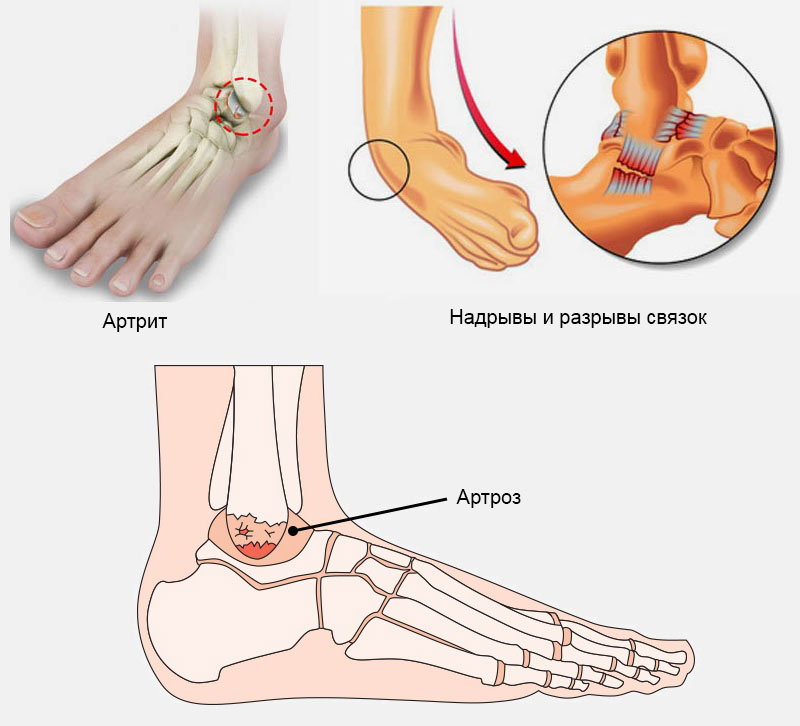

Артроз голеностопного сустава 2 степени схема лечения